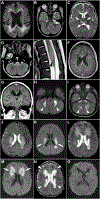

Purpose: Mendelian etiologies for acute encephalopathies in previously healthy children are poorly understood, with the exception of RAN binding protein 2 (RANBP2)-associated acute necrotizing encephalopathy subtype 1 (ANE1). We provide clinical, genetic, and neuroradiological evidence that biallelic variants in ribonuclease inhibitor (RNH1) confer susceptibility to a distinctive ANE subtype.

Methods: This study aimed to evaluate clinical data, neuroradiological studies, genomic sequencing, and protein immunoblotting results in 8 children from 4 families who experienced acute febrile encephalopathy.

Results: All 8 healthy children became acutely encephalopathic during a viral/febrile illness and received a variety of immune modulation treatments. Long-term outcomes varied from death to severe neurologic deficits to normal outcomes. The neuroradiological findings overlapped with ANE but had distinguishing features. All affected children had biallelic predicted damaging variants in RNH1: a subset that was studied had undetectable RNH1 protein. Incomplete penetrance of the RNH1 variants was evident in 1 family.

Conclusion: Biallelic variants in RNH1 confer susceptibility to a subtype of ANE (ANE2) in previously healthy children. Intensive immunological treatments may alter outcomes. Genomic sequencing in children with unexplained acute febrile encephalopathy can detect underlying genetic etiologies, such as RNH1, and improve outcomes in the probands and at-risk siblings.